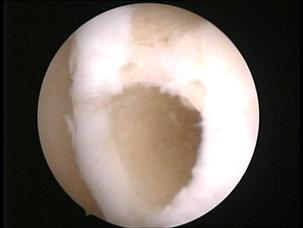

Examinarea artroscopica a genunchiului ramine standardul de aur in diagnosticarea si evaluarea leziunilor cartilajului articular. Examenul artroscopic permite evaluarea suprafetei cartilajului, a rezistentei la presiune, dar mai ales a marimii si profunzimii zonei leziunii condrale. Numeroase sisteme de clasificare a leziunilor cartilajului articular au la baza examinarea artroscopica directa a acestuia (vezi capitolul 2).

Examinarea artroscopica a cartilajului permite evaluarea mai multor caracteristici ale acestuia. Rezistenta cartilajului la presiune se efectueaza cu ajutorul exploratorului (probe), si se refera la forta cu care acesta este impins inapoi dupa ce presiune a incetat. Persistenta unei depresiuni condrale este semn de "inmuiere" a cartilajului. Artroscopic se evalueaza si culoarea cartilajului care normal este alba, lucioasa, cu usoara tenta galbuie. Cartilajul artrozic are o culoare galbuie marcata, este mat.

La examinarea artroscopica suprafata cartilajului este neteda, lucioasa, o fara discontinuitati. Pierderea luciului, prezenta unor depresiuni, fisuri, fibrilatii, delaminari sint semne de leziune. De asemenea, o zona de ingrosare a cartilajului, depresibila la examinarea cu exploratorul, este semnul unei leziuni profunde: "blister".

Fig. 1.13. Imagini artroscopice - leziuni osteocondrale stadiu III B si C ICRS la nivelul condilului femural si la nivelul patelei |